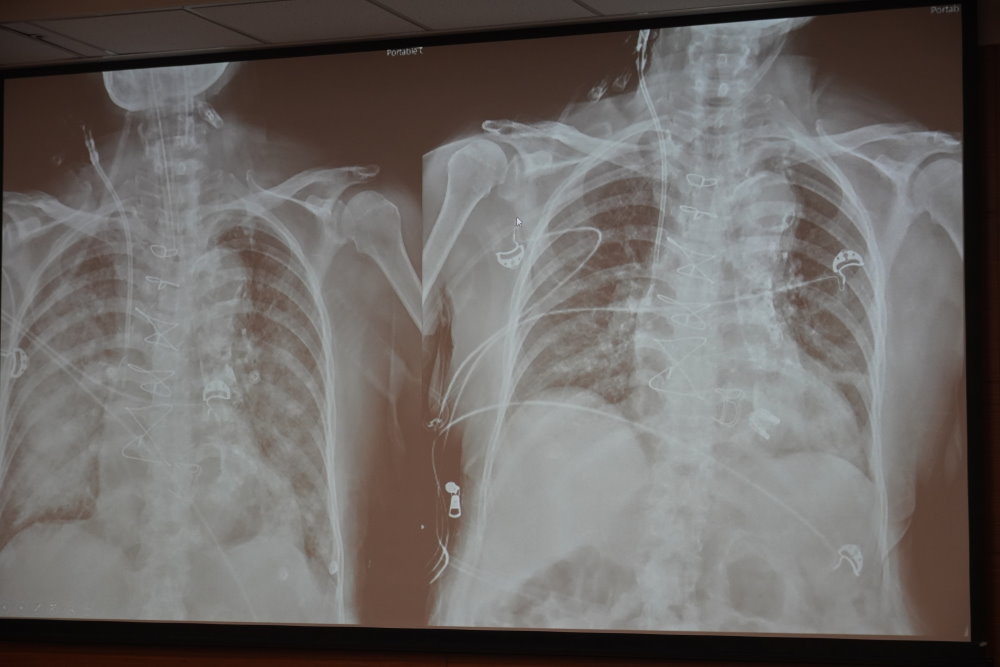

除了急性情況,成大醫院處理慢性瓣膜病變也具備豐富經驗。另一位58歲女性,近期幾個月行走時容易喘,心臟超音波發現中度至重度二尖瓣狹窄,瓣膜壓力差高達18 mmHg,嚴重影響血液流通。團隊安排經皮經導管二尖瓣球囊擴張術(PTMV)後,壓力差降至3 mmHg,病人喘的情況顯著改善,恢復良好,不需住院。

86歲的男性,則因嚴重主動脈瓣狹窄,導致頭暈與體力下降,就診時已影響日常行走能力。考量年齡與共病情況,心臟團隊決定採行經導管主動脈瓣置換術(TAVR)。手術過程順利,術後數日病人即下床活動,目前行走自如,生活品質大幅提升。